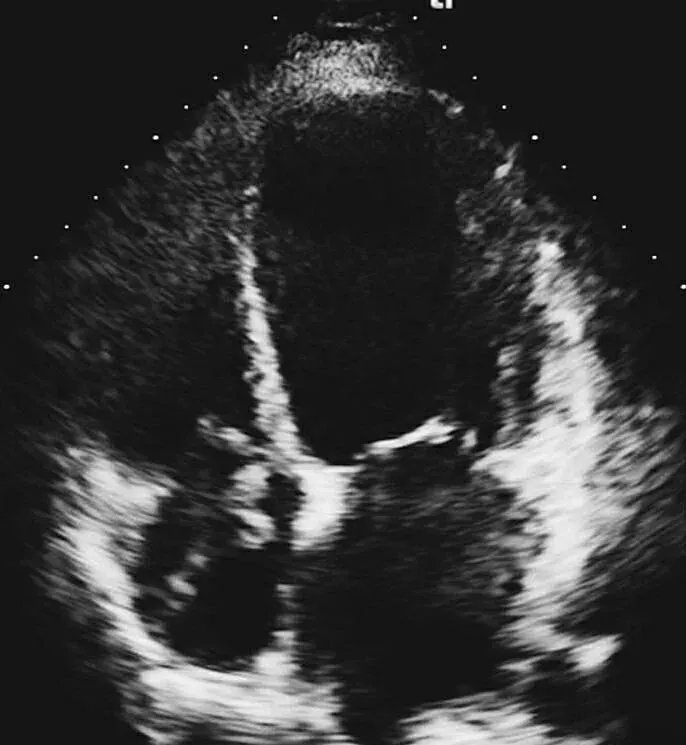

超声心动图:左心室舒张末内径64mm,LVEF 35%,右房内可见不规则条索状、团状等回声,随心脏摆动,舒张期可进入右心室,考虑右房内血栓可能,节段性室壁运动障碍(室间隔、左室心尖部、侧壁心尖段、前壁心尖段、下壁),心尖部室壁瘤形成。

图2 抗凝前后超声心动图对比

A图为入院心脏超声心尖四腔切面,可见右房内疑似血栓影,舒张期可进入右心室内;B图为抗凝治疗1周后复查,可见右房内血栓消失